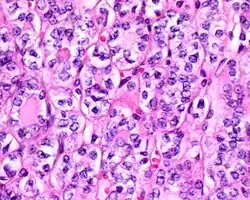

4) Must have the characteristic nuclear features of papillary thyroid carcinoma, although sometimes the features are patchy in distribution without all of the tumor showing those features. The nuclear features can be divided into three main categories:

- Nuclear size and shape: nuclear enlargement, nuclear elongation, and nuclear overlapping and crowding. Loss of nuclear polarity, with nuclei at the lumen, middle, or basal zone of the cells is also a helpful finding.

- Nuclear membrane irregularities: irregular nuclear contours, nuclear grooves and folds, "rat-bites" or demi-lune formations, and the presence of intranuclear cytoplasmic inclusions.

- Nuclear chromatin characteristics: nuclear chromatin clearing, often with condensation or margination along the nuclear membranes, resulting in accentuated nuclear margins, glassy nuclei, or fine, even delicate, powdery nuclear chromatin.